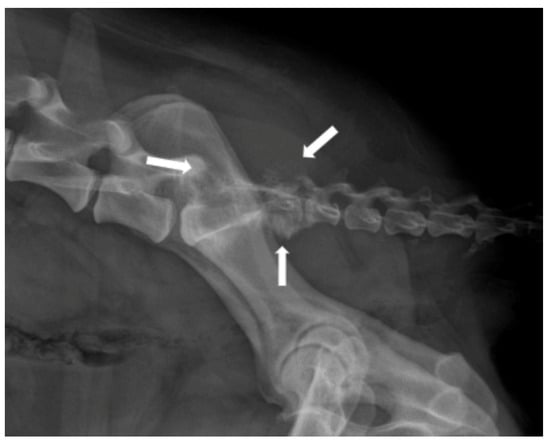

2.2. Cerebrovascular Disease